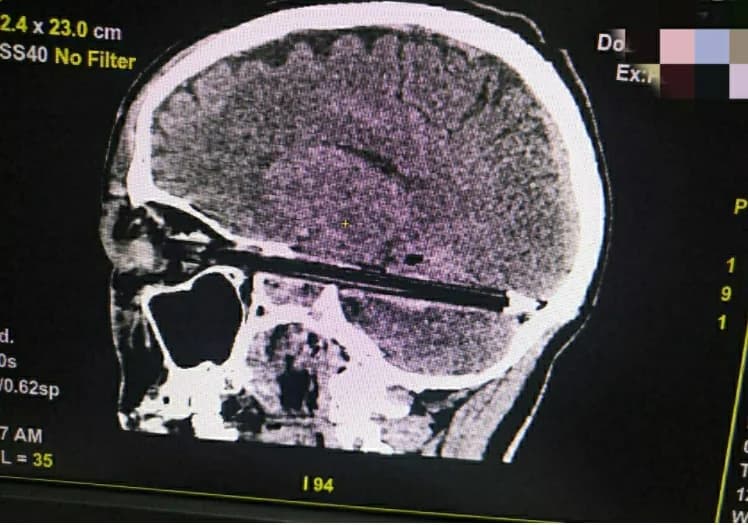

سجلت منطقة روستوف في روسيا حادث غريب لاستقرار قلم في جمجمة رجل دون سبب معروف.

وذكر الأطباء أن القلم دخل في جمجمة الرجل حتى وصل إلى نهاية مؤخرة الجمجمة من خلال عينه.

وأضاف الأطباء أن الوقت لم يسعفهم لسؤال المريض عن سبب وجود القلم في جمجمته، لكنهم نجحوا في استخراج القلم من رأسه.